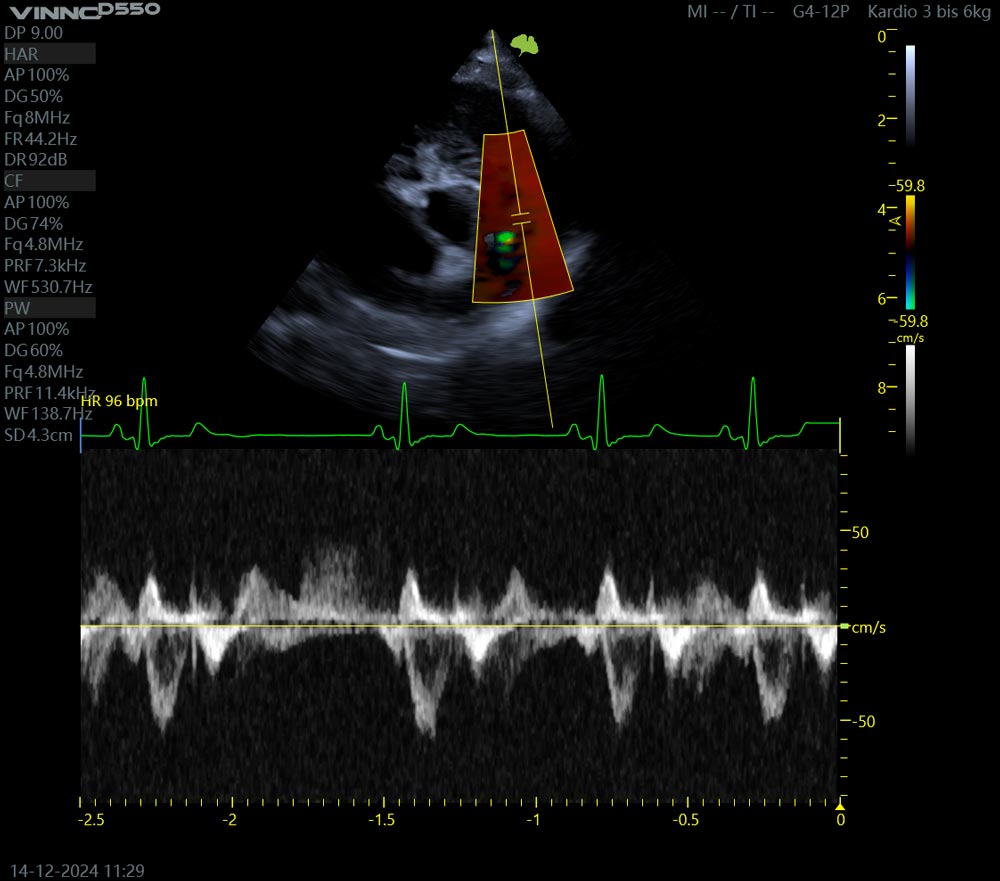

Ultraschall und Herzultraschall (Echokardiographie)

Die Doppler-Sonographie ermöglicht die farbliche Darstellung von Gefäßen im Körper und von fehlerhaften Flüssen an den Herklappen. Beim Herzultraschall bzw der Echokardiographie werden die Herzmuskelleistung und die Herzklappen untersucht. Weiterlesen...

Kardiologie

Speziell erwähnen möchten wir den Bereich der Kardiologie. Hierzu gehört insbesondere der Herzultraschall, Echokardiographie genannt, zur Untersuchung der Herzmuskelleistung, der großen Gefäße des Herzens und der Klappenfunktion. Hierunter fällt auch die Abklärung angeborener Anomalien. Mit Hilfe der Doppler-Sonographie, der farblichen Darstellung von Blutflüssen, gelingt eine Beurteilung der Flüsse in Gefäßen im Körper und eine Darstellung der Funktion der Herzklappen.

Das EKG zur Untersuchung von Rhythmusstörungen und Problemen bei der Reizleitung komplettiert die Diagnostik der Kardiologie. Im digitalen Röntgen können cardialbedingte Stauungen, Lungenödeme und Tumore wie Herzbasistumore dargestellt werden. Mittels Ultraschall können wir auch herzbedingte Stauungen in die Brust- und Bauchhöhle sichtbar machen.